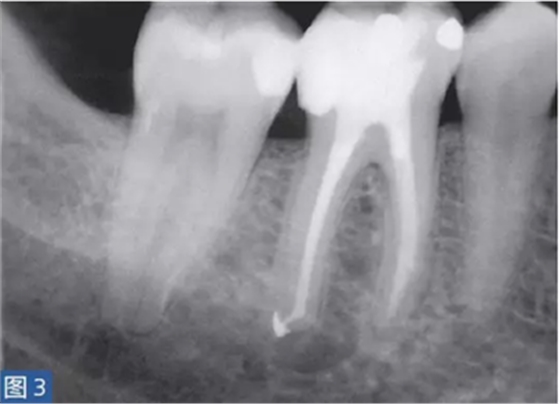

從牙髓炎過(guò)渡到根尖周炎(圖2 和3)的發(fā)生速度非???,牙齒表現(xiàn)可能從正常到對(duì)冷、熱和電刺激的反應(yīng)越來(lái)越強(qiáng)。當(dāng)牙髓已經(jīng)完全壞死時(shí),通常會(huì)顯示對(duì)牙髓電活力測(cè)試無(wú)反應(yīng)。牙齒可能會(huì)有伸長(zhǎng)感,用手指或口鏡柄施加壓力或者振動(dòng)牙齒會(huì)觸發(fā)非常嚴(yán)重的疼痛。放射學(xué)檢查可能存在透射區(qū)及根周膜間隙增寬,通常硬骨板和牙周韌帶沒(méi)有病理學(xué)特征。

圖2: 46 牙齒SAP。術(shù)前X 線片,該牙齒在其他醫(yī)生處已行齲齒治療。患者訴牙齒有明顯的咬合痛以及強(qiáng)烈的冷熱刺激敏感癥狀。放射學(xué)檢查,近中根根周膜間隙略增寬。

圖3: 46 牙齒SAP。根管治療6個(gè)月后。